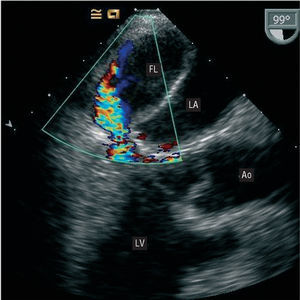

During the immediate postoperative period, the patient experienced hemodynamic instability and difficulty weaning from the intra-aortic contrapulsation balloon. On transthoracic echocardiography, the mitral prosthesis showed no alterations and left ventricular systolic function was preserved. Because there was no correlation between the transthoracic echocardiography findings and the patient's clinical status, transesophageal echocardiography was performed. The examination revealed a false chamber in the interior of the left atrium that was formed by the dissected posterior atrial wall and occupied nearly the entire true lumen (Figure 1). In addition, retrograde systolic flow was observed in the interior, coming from the posterior wall of the left ventricle below the prosthesis. There was no evidence of a communication between the true and false lumen, or perivalvular regurgitation (Figure 2).

Figure 2.